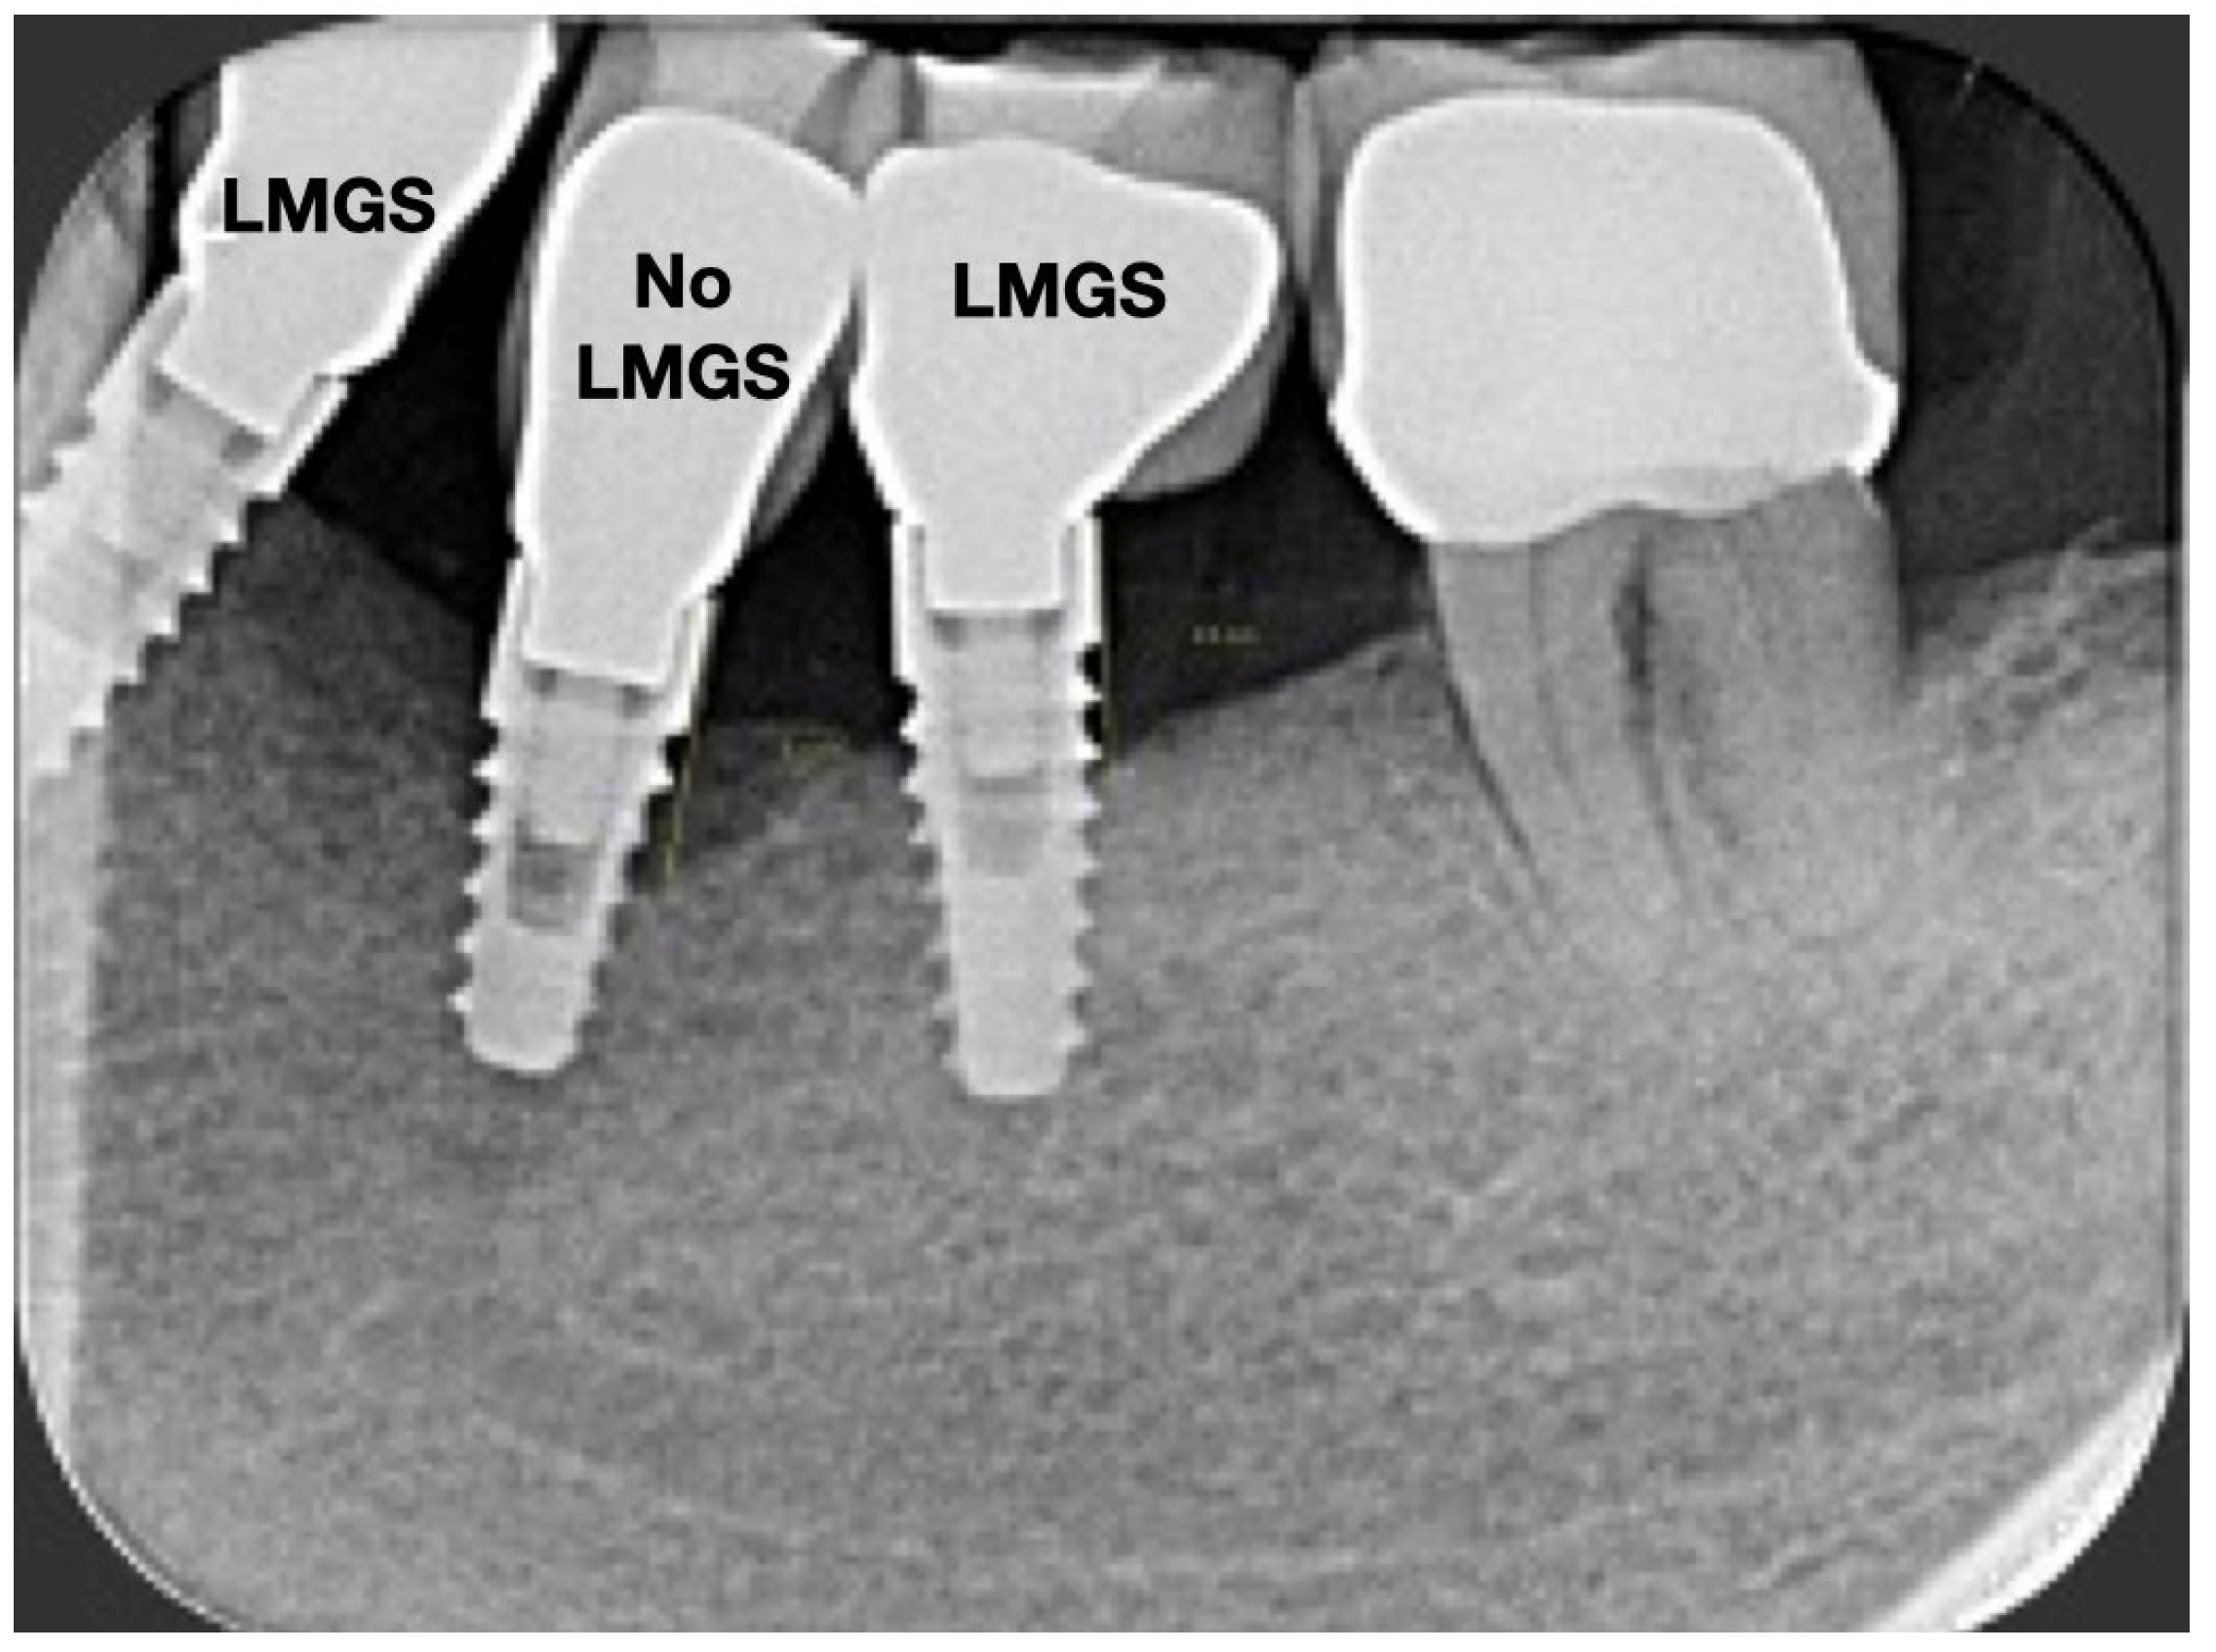

A total of 164 LMGS implants (37.4%) and 195 no-LMGS implants (42.1%) presented PIM. Differences between LMGS implants and no-LMGS implants were not statistically significant (p > 0.05). A total of 28 (6.3%) LMGS implants and 98 (21.1%) no-LMGS implants demonstrated P with a statistically significant difference (p < 0.01). Figure 2, Figure 3, Figure 4 and Figure 5 report examples of radiographs during follow-up.

Figure 3.

Radiograph of the same three (3) implants at 5 years. (LMGS = with a laser-microgrooved collar surface; No-LMGS = without a laser-microgrooved collar surface).